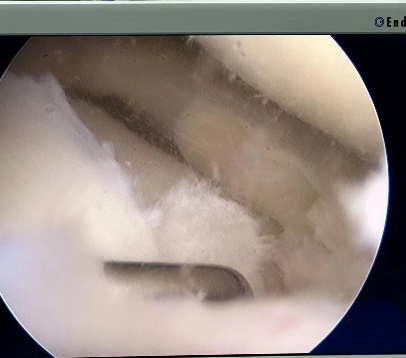

病例七:患者,女,36岁,因“左膝关节疼痛活动受限5天”入院。诊断:左膝外侧半月板撕裂;行左膝关节镜探查+滑膜清理+外侧半月板成形术;手术顺利,术后恢复良好,顺利出院。

左膝外侧半月板撕裂 术中关节手术图片